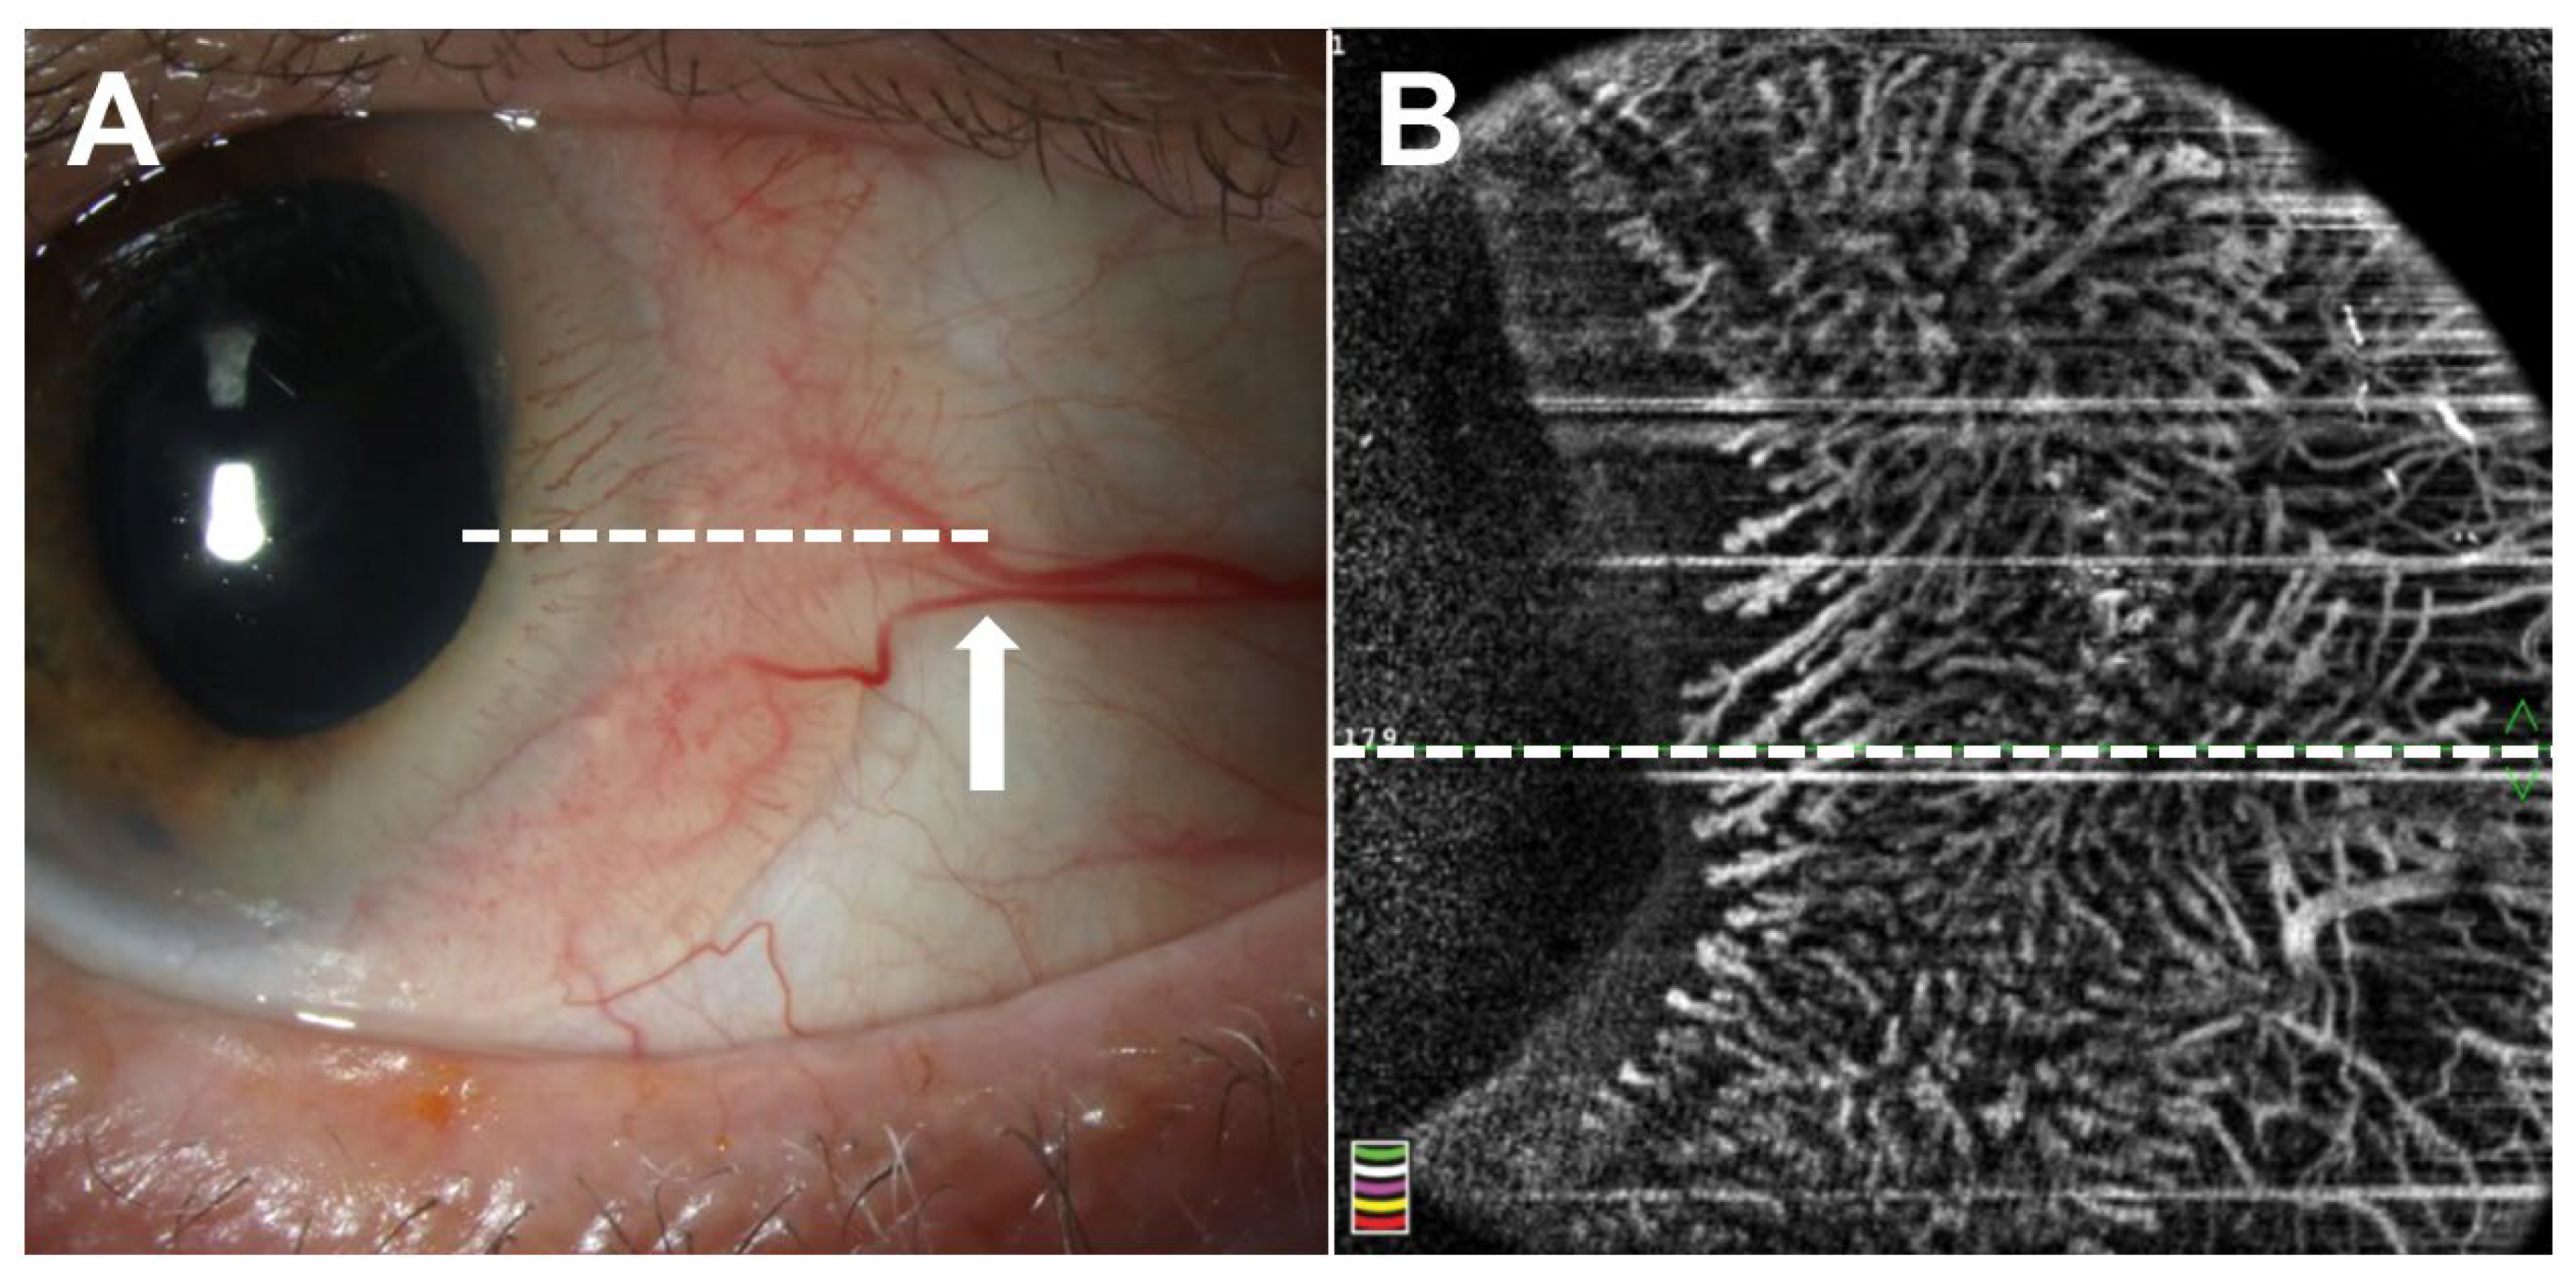

3.2. Current Applications of OCTA

- Tahiri Joutei Hassani, R.; Liang, H.; El Sanharawi, M.; Brasnu, E.; Kallel, S.; Labbe, A.; Baudouin, C. En-face optical coherence tomography as a novel tool for exploring the ocular surface: A pilot comparative study to conventional B-scans and in vivo confocal microscopy. Ocul. Surf. 2014, 12, 285–306. [Google Scholar] [CrossRef]